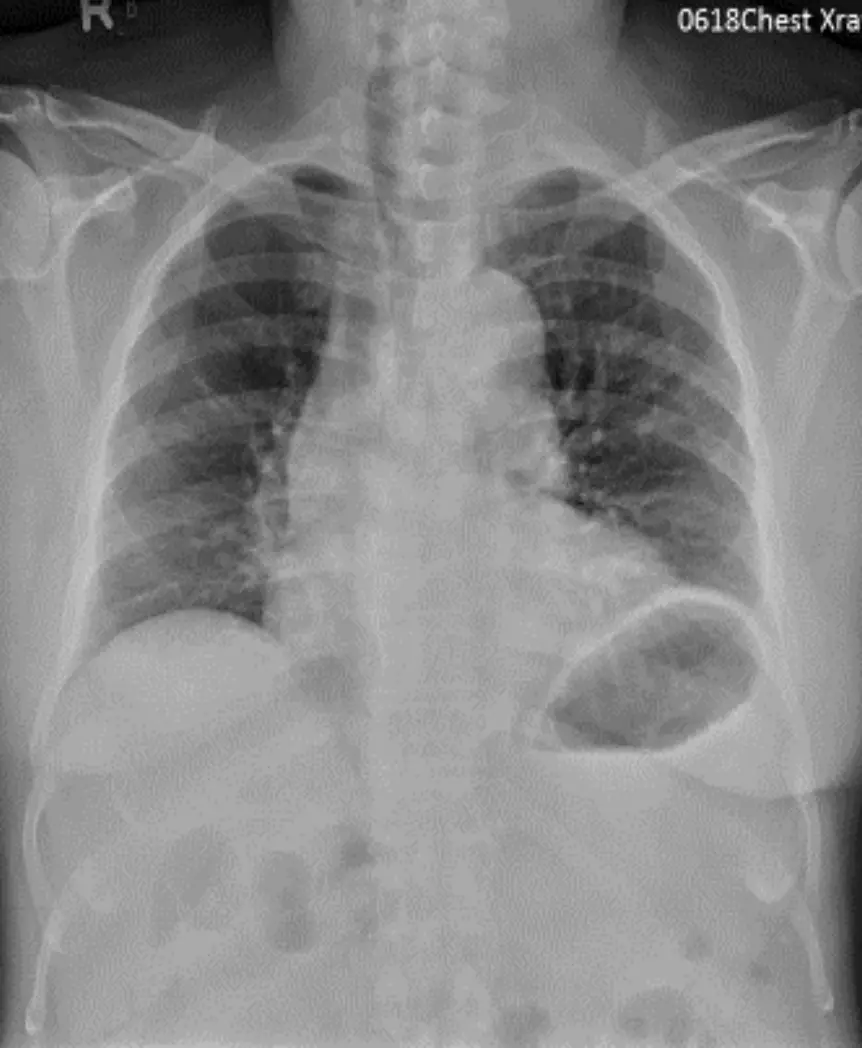

胸部X光:左右肺野無肺部浸潤或肺水腫,心臟輪廓並未顯著增大。上縱隔可見中等程度寬窄變化,提示左側頸部及縱隔淋巴結腫大所致之影像。